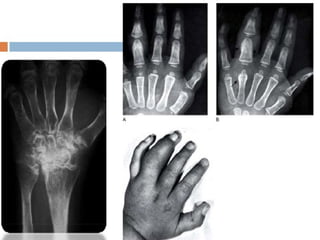

 Poignets et mains : au poignet et au carpe la « tumeur

dorsale du carpe » avec voussure de la face

d'extension .

La limitation de la mobilité porte d'abord sur

l'extension, ensuite sur les mouvements de flexion et

de latéralité.

 Aux doigts, l'atteinte articulaire intéresse les (IPP) qui

sont gonflées :aspect de « doigt en fuseau », les

metacarpophalangiennes (MCP) peuvent être

intéressées, se manifestant par une réduction de la

mobilité, un flessum et une douleur à la pression de

l’articulation.

Forme avec présence

de facteur rhumatoïde,

ayant débuté à l’âge de 6 ans   .

A. 1 an d’évolution    B. 3 ans d’évolution :

: ostéoporose          ostéoporose,                C. 5 ans d’évolution : bloc

mineure.               pincements articulaires,    carpien presque complet.

irrégularités des points

d’ossification.